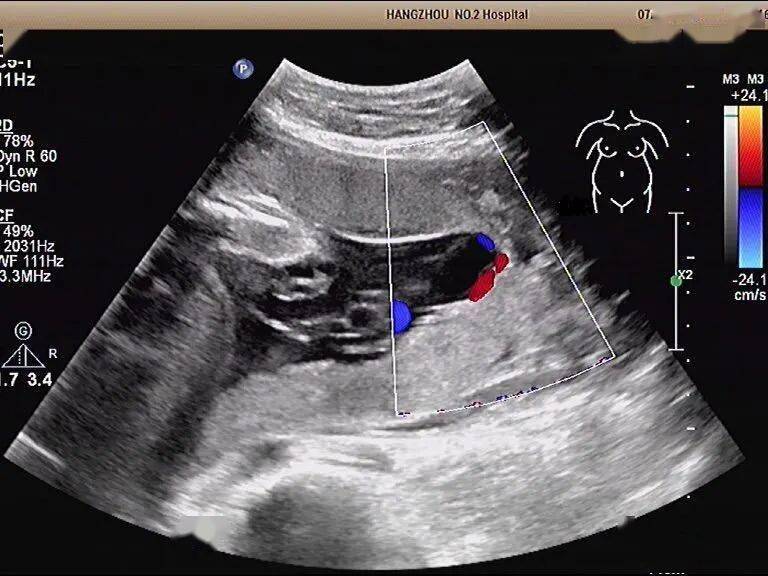

脐带帆状入口时,部分脐带血管走行于胎膜内,或有 副胎盘时,部分胎儿

【讨论】帆状合并副胎盘

注意,主胎盘娩出后若副胎盘残留宫腔,可致产后出血和感染.